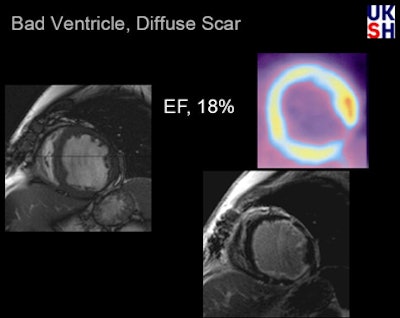

| In a patient with severely impaired LV function (EF 18%), PET reveals a small transmural scar at the inferior lateral wall, as well as an apparent FDG uptake deficit. MRI of the same patient shows a small transmural scar and a large subendocardial scar indicating typical ischemic cardiomyopathy. All data and images courtesy of Dr. Peter Hunold. |